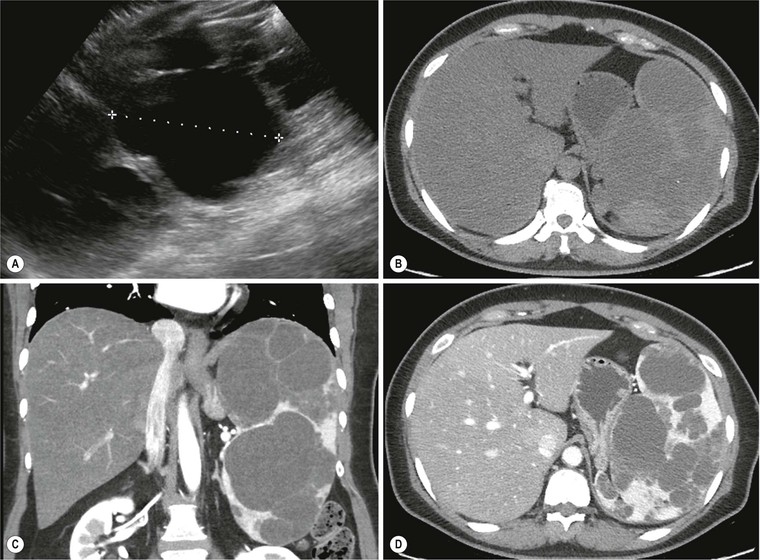

Contrast-Enhanced Sonography of Intrapancreatic Accessory Spleen in Six ...